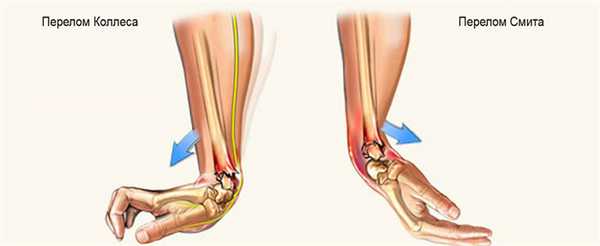

- Перелом Смита (сгибательный перелом). Причиной травмы служит падение на вытянутую руку, на ее тыльную сторону. Кость ломается и при этом происходит смещение костных отломков в сторону ладони.

- Перелом Коллеса (разгибательный перелом). Повреждение случается при падении человека на ладонь, наблюдается смещение костных отломков в сторону большого пальца и тыльной поверхности кисти.